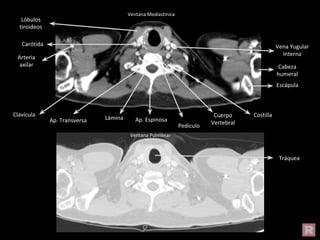

Ventana Mediastínica

Tráquea

Vena Yugular

Interna

Carótida

Arteria

axilar Cabeza

humeral

Escápula

Costilla

Clavícula

Ap. Transversa Lámina Ap. Espinosa

Pedículo

Cuerpo

Vertebral

Lóbulos

tiroideos